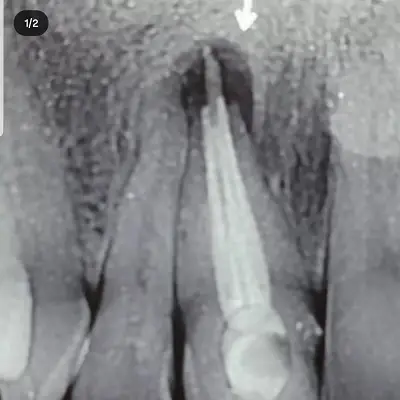

بهترین دکتر درمان ریشه در شهریار خدمات تخصصی عصبکشی را با هدف حفظ دندان طبیعی و کاهش درد بیماران ارائه میدهد. تشخیص دقیق عفونت ریشه با استفاده از تصویربرداری پیشرفته، باعث میشود درمان با دقت بالا و ماندگاری بیشتر انجام شود.

درمان ریشه دندانهای تککاناله و چندکاناله، درمان مجدد ریشههای عفونی و کنترل دردهای شدید دندانی از مهمترین خدمات متخصص درمان ریشه در شهریار است. این خدمات بهگونهای انجام میشوند که از گسترش عفونت و نیاز به کشیدن دندان جلوگیری شود.